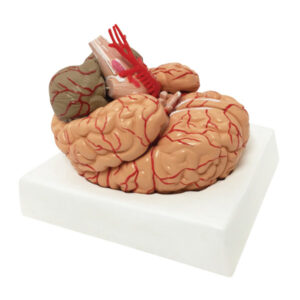

Modelo de artérias cerebrais